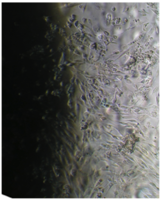

Культуру дермальных фибробластов получали из кожно-мышечной ткани, а культуру мезенхимальных стромальных клеток – из фрагментов крыши черепа абортусов сроком 6-10 недель методом первичных эксплантатов (рис. 1, 2).

Вид монослоя и структура клеток не отличались от обычных в течение всех четырех суток наблюдения (рис. 32).

Наблюдение через сутки показало, что фибробласты хорошо пристают к дну культуральной чашки, образуют равномерный монослой с плотностью 311 клеток/мм².

Фибробласты были распластаны по дну чашки, имели обычную для этих клеток удлиненную форму, 2-4 отростка, клеточная и ядерная оболочки четко контурировали.

Цитоплазма представлялась гомогенной (рис. 33). Большинство клеток имели одно центрально расположенное ядро правильной округлой формы с 1 или 2 ядрышками.